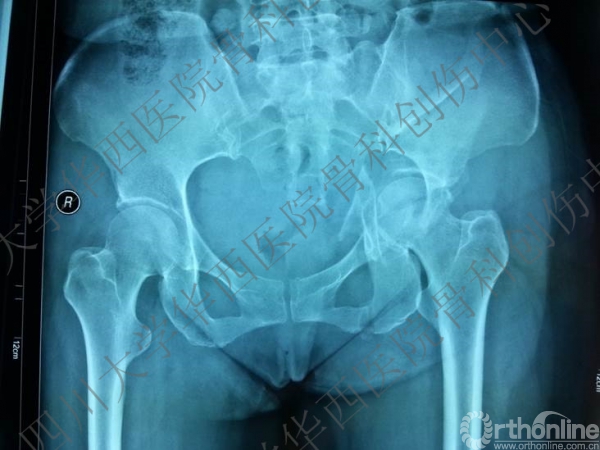

基本资料: 患者,女性,45岁,车祸伤致左髋疼痛伴活动障碍5+天。患者行走时被小轿车撞伤,小轿车逃逸,被同村村民送来我院。

查体:神清合作,左髋疼痛,不能活动,足背动脉可扪及,踝关节及足趾活动正常。

诊断:左髋臼双柱骨折。

入院后行左股骨髁上牵引,积极术前准备,做CT,证实双柱骨折的诊断。